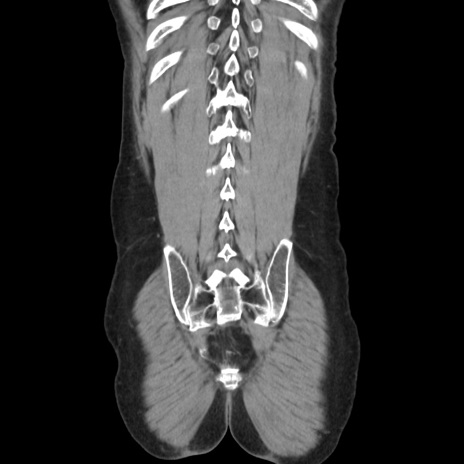

症例37(冠状断像)

【症例】40歳代 男性

【主訴】腹痛

【現病歴】4時間ほど前に電車に乗車中に臍部上より腹痛出現。徐々に増悪し起立困難となり、救急外来受診。生ものは数日食べていない。今朝お雑煮を食べた。

【身体所見】BT 36.8℃、BP 117/84mmHg、HR 91/min、SpO2 97%、苦悶様、腹部:臍上部広範囲圧痛あり、反跳痛±

【データ】WBC 8100、CRP 0.03